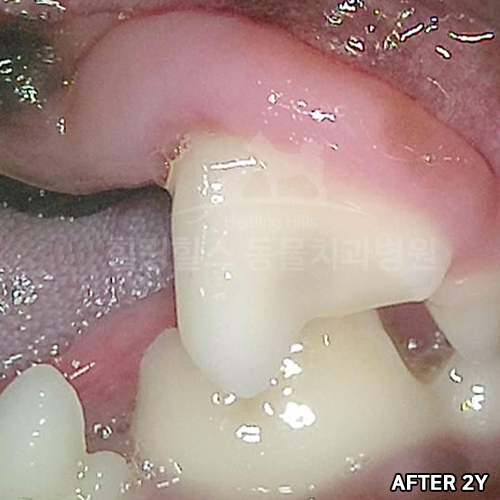

[강아지 치아파절 치료 후 4년 경과모습]

샘플